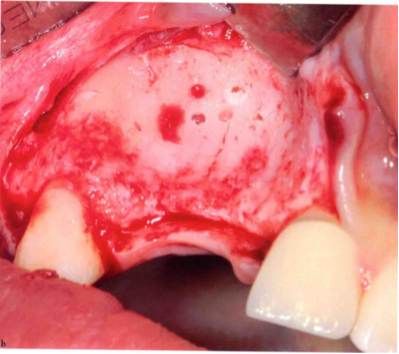

去皮质化

(四)受区预备

对受区进行预备,如表面修整、去皮质化等,增加与移植骨块的接触面积和血供,促进愈合。